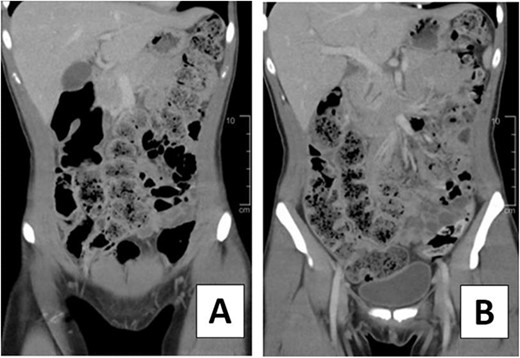

A 23-year-old female presented to the emergency department with right lower quadrant abdominal pain. She also experienced nausea, fever, chills, and malaise. Additionally, she reported a history of chronic constipation, with her last bowel movement occurring several days prior to her hospital visit. On physical examination, tenderness was noted at McBurney’s point and a positive Rovsing sign was observed. Patient had a leukocytosis of 14 000 and an abdominal computed tomography (CT) with intravenous contrast was significant for moderate to large proximal fecal load and a normal-appearing appendix (Fig. 1).

CT scan of 23-year-old female on hospital Day 1. (A, B) Coronal views depicting moderate to large fecal load.